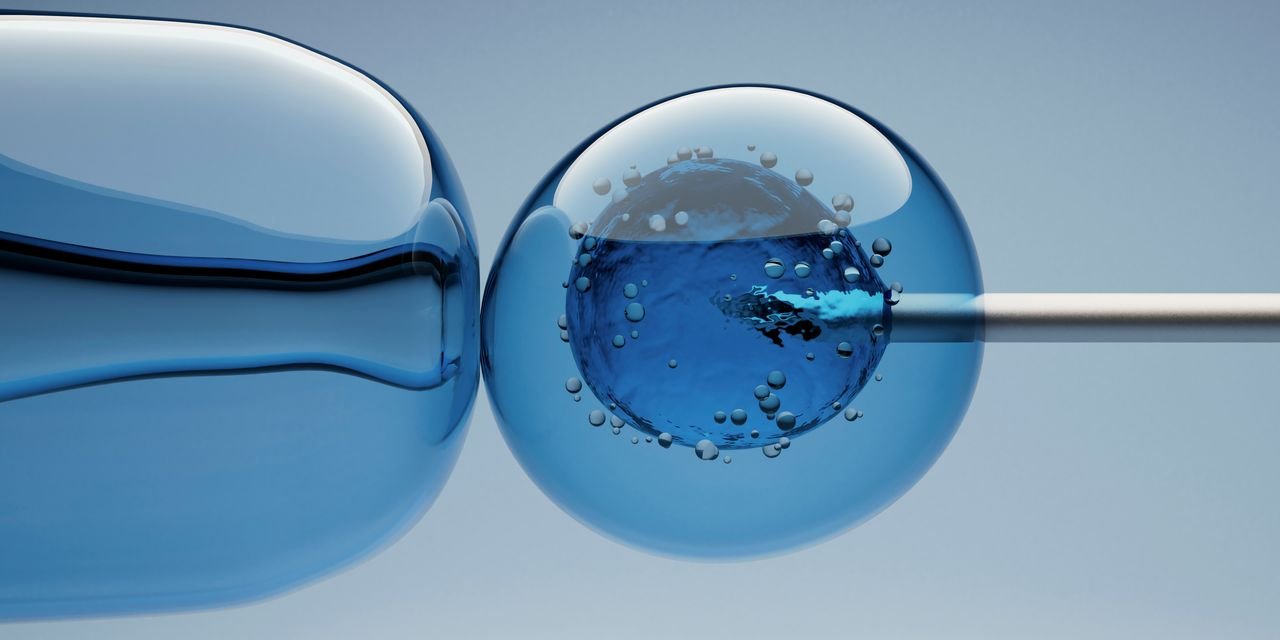

A New partnership Between Costco, Sesame (a cash-for-pay health care marketplace), and IVI RMA (a network of fertility clinics) aim to reduce some of the major barriers Americans face when seeking fertility treatment. For $99 a month with a Costco membership (or $119 without), you can meet with a doctor of your choice virtually on the Sesame platform to get a fertility check and make a diagnosis, the companies announced Monday. This means bypassing the often months-long wait times for an appointment with a specialist. From there, Sesame connects you with an IVI RMA clinic in your area — more than 85% of which are located within 25 miles of Costco — to coordinate treatments like IVF (in vitro fertilization) or intrauterine insemination (IUI), at discounted rates, while also discounting medications through Costco’s specialty pharmacy.

There is currently a large gap between the number of people who may seek fertility treatment in the United States — for example, those struggling with infertility or recurrent miscarriage, and members of the LGBTQ+ community — and Those who can access it. “The biggest barrier when it comes to access is cost and affordability, which is undeniable,” says Dr. Levine. The cost of IVF can be upwards of $5,000 or $6,000 with insurance, and up to $30,000 without insurance, if you factor in lab work and related services and medications. Less than half of the states It has a mandate that requires private insurance companies to cover fertility care.

There’s also the problem of finding that care, even if you can afford it. A Study 2023 It is suggested that demand is as high as 2 million per year for IVF cycles in the United States, which would require only 1,250 reproductive endocrinologists in the United States to do approximately seven times the number of cycles they currently complete. The fact that many Costco members live near an IVI RMA clinic is key, since “fertility patients also have to have regular appointments, up to six appointments over a two-week period,” says Dr. Levine. (The partnership will be less beneficial for people who live in New York City or other cities without an IVI RMA clinic.)